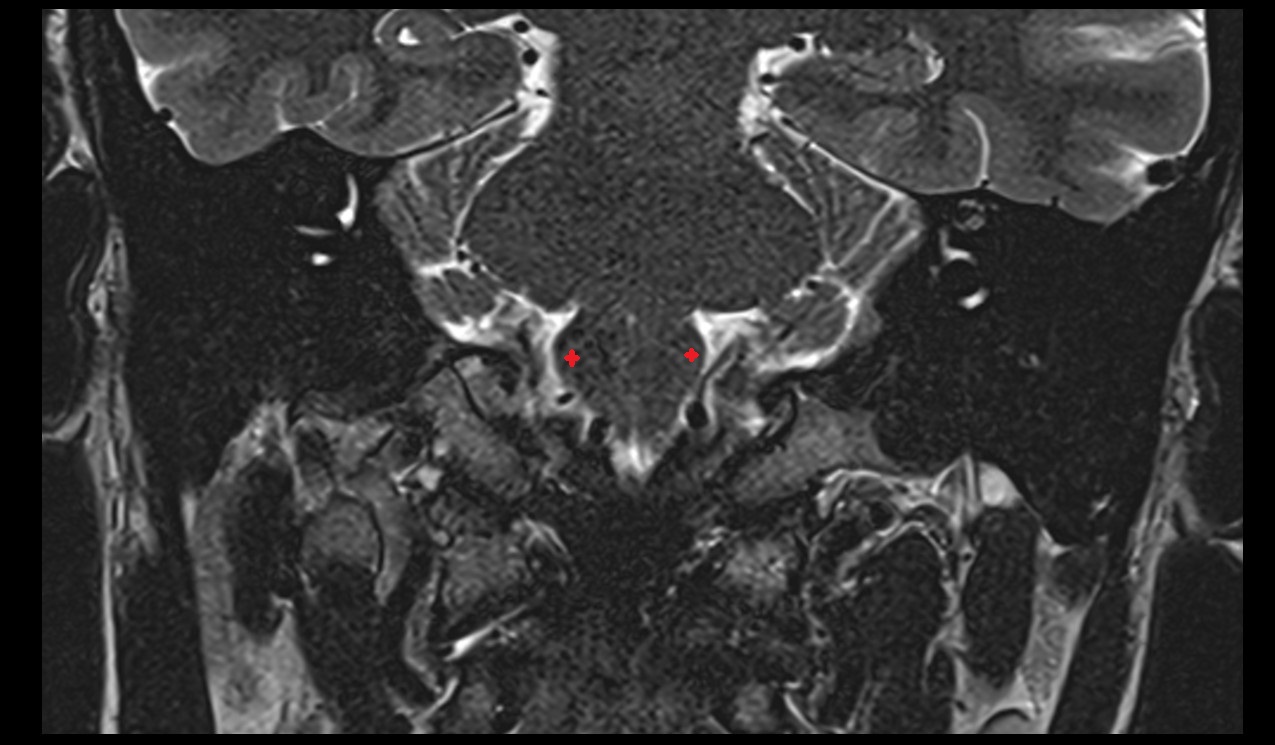

- Temporomandibular joint

- Mandibular condyle

- Mandibular fossa

- Articular disc of temporomandibular joint

- Articular eminence